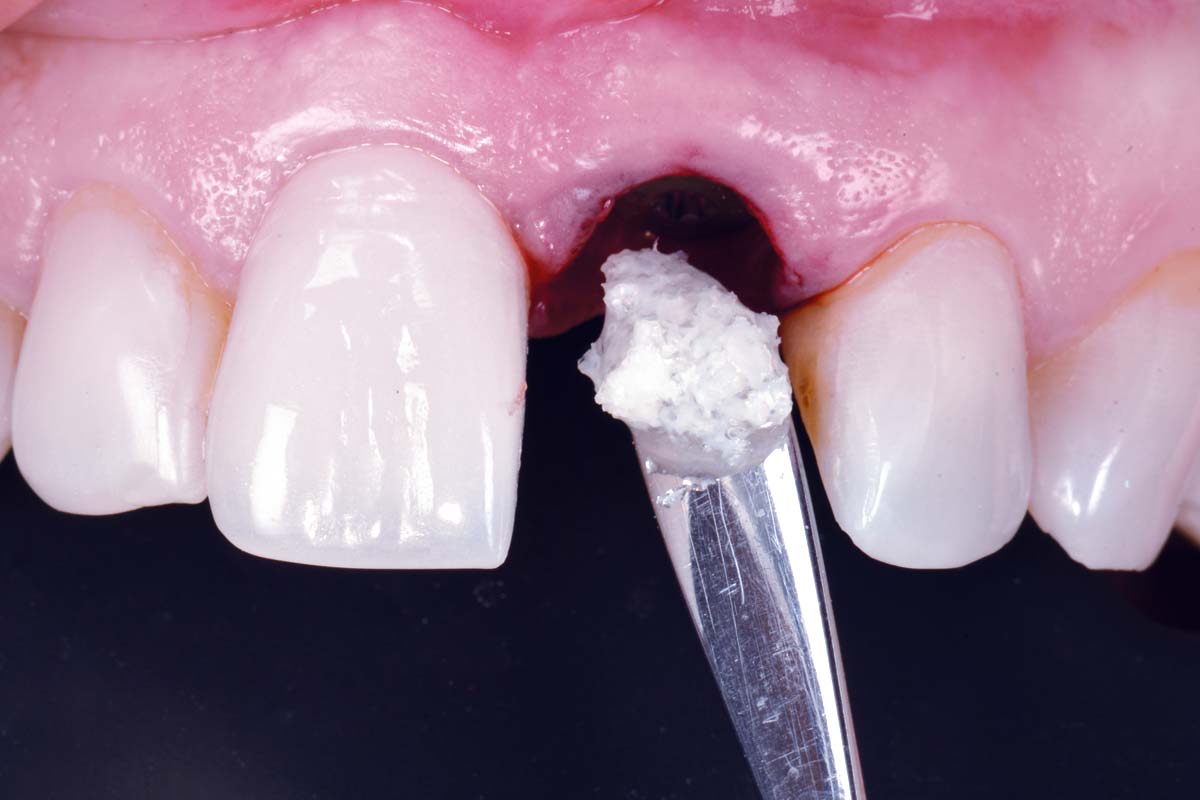

Immediate implant placement using cerabone® and collagen fleece - Dr. D. Jelušić

Pre-operative situation showing tooth 21 with deep periodontal pocket. Tooth presented with mobility grade III.